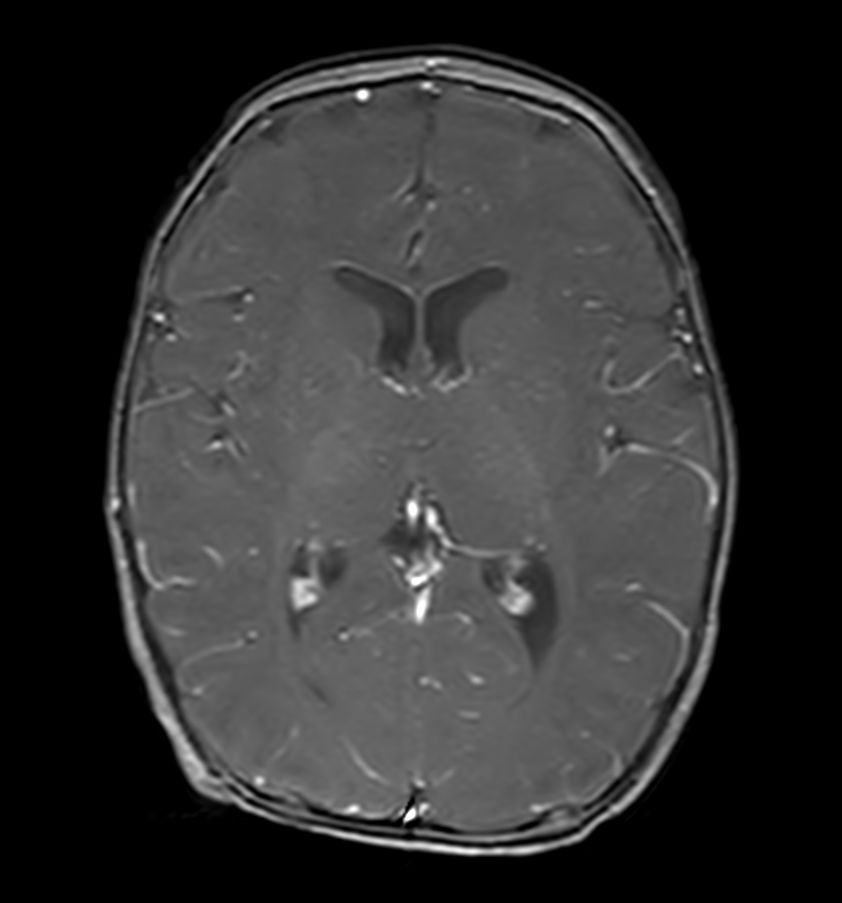

3D T1w TFE SPIR - Axial reformat (post-gado)

3D T1w TFE SPIR - Coronal reformat (post-gado)